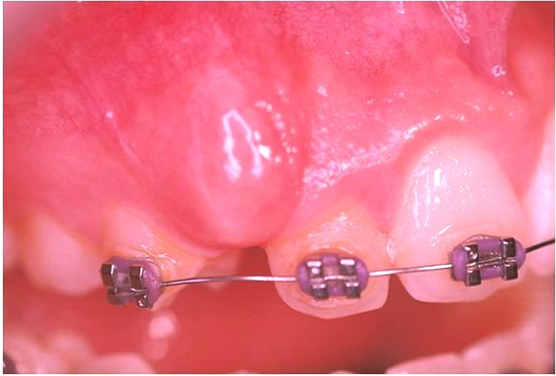

Νεαρός ασθενής που βρισκόταν υπό ορθοδοντική θεραπεία εμφάνιζε έγκλειστο τον κυνόδοντα άνω αριστερά.

Με τη χρήση του Nd-Yag laser έγινε αποκάλυψη του κυνόδοντα, ώστε να γίνει δυνατή η ορθοδοντική μετακίνηση (μετοποθέτηση αγκυλίου-Bracket)

Αρχική κλινική εικόνα